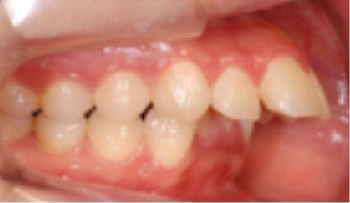

• 총생(Crowding) 치아가 삐뚤게 남.

Before

After